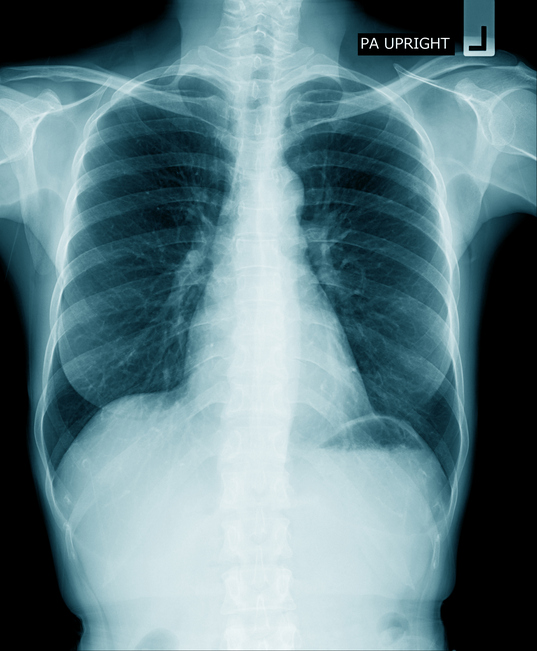

Un equipo de investigadores ha descifrado el motivo por el que la inmunoterapia es efectiva en determinados cánceres de pulmón y ha concluido que aquellos tumores que presentan una huella epigenética concreta responden «muy bien» a la quimioterapia en comparación a los que carecen de ella.

Este estudio clínico ha mostrado un patrón que permite predecir la respuesta de la inmunoterapia en el cáncer de pulmón con el anticuerpo anti-PD-1, la inmunoterapia más usada en oncología. Esta huella, a la que los expertos han llamado EPIMMUNE, se encuentra en un tercio de los cánceres de pulmón y presenta un enriquecimiento en los linfocitos T y B.